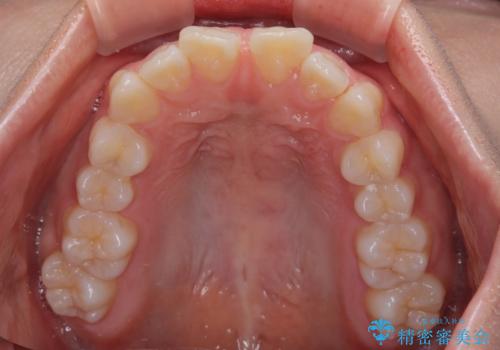

深い咬み合わせによる隙間 インビザライン矯正でコンプレックスを改善

- 上の前歯の隙間を気にして来院された患者様です。

インビザラインにより、上下の歯列を側方に拡大しつつ、前歯の隙間を閉じていくこととしました。

隙間の原因は強い咬合力や舌の突出癖、小帯の異常付着などがありますが、舌のトレーニングをしっかりと行いながら、装着時間を遵守して装着していただいたおかげで、スムーズに治療を終えることができました。